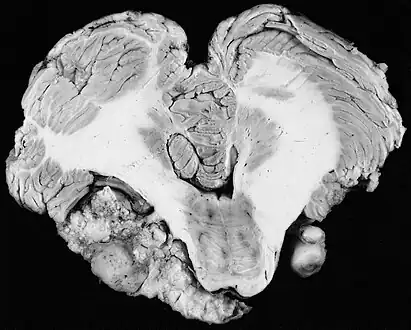

There have been cases of tumors that were actually asymptomatic until very large and at a critical stage. Tumor growth rates are highly variable: some small VSs (perhaps 50%) do not grow at all; some few grow for a time and then shrink; some appear dormant but suddenly grow rapidly. In general, although studies differ, VSs that grow are slow-growing at an average rate of 1.2 to 1.9 mm per year. IAC tumors that grow beyond 1.5 cm in diameter expand into the relatively empty space of the cerebellopontine angle, taking on the characteristic 'ice-cream-cone' appearance seen on MRIs. As 'space-occupying-lesions,' the tumors can reach 3 to 4 cm or more in size and infringe on the facial nerve (facial expression) and trigeminal nerve (facial sensation). Hearing loss and spells of vertigo may occur. Very large tumors are life-threatening when they press on the cerebellum or cause brainstem compression. Late symptoms of very large VS include headache, nausea, vomiting, sleepiness, mental confusion and eventually coma.[5][6]

In the early 1900s the mortality rate for VS surgery was in the range of 75 to 85%. Surgeons typically delayed invasive intervention as long as possible as a last resort. Harvey Cushing (1869–1939) is known as 'the father of neurosurgery for VS.' His basic study published in 1917 was entitled Tumors of the Nervus Acusticus and the Syndrome of the Cerebellopontine Angle. Cushing perfected the retrosigmoid surgical approach, and by doing suboccipital craniotomy and subtotal removals he was able to reduce mortality to 4% by 1931. Cushing worked at Brigham Hospital in Boston. An equally famous specialist for VS at Johns Hopkins in Baltimore was Walter E. Dandy (1886–1946), a former pupil of Cushing who advocated total tumor removals. In 1931, he reported a complete removal with preservation of the facial nerve.